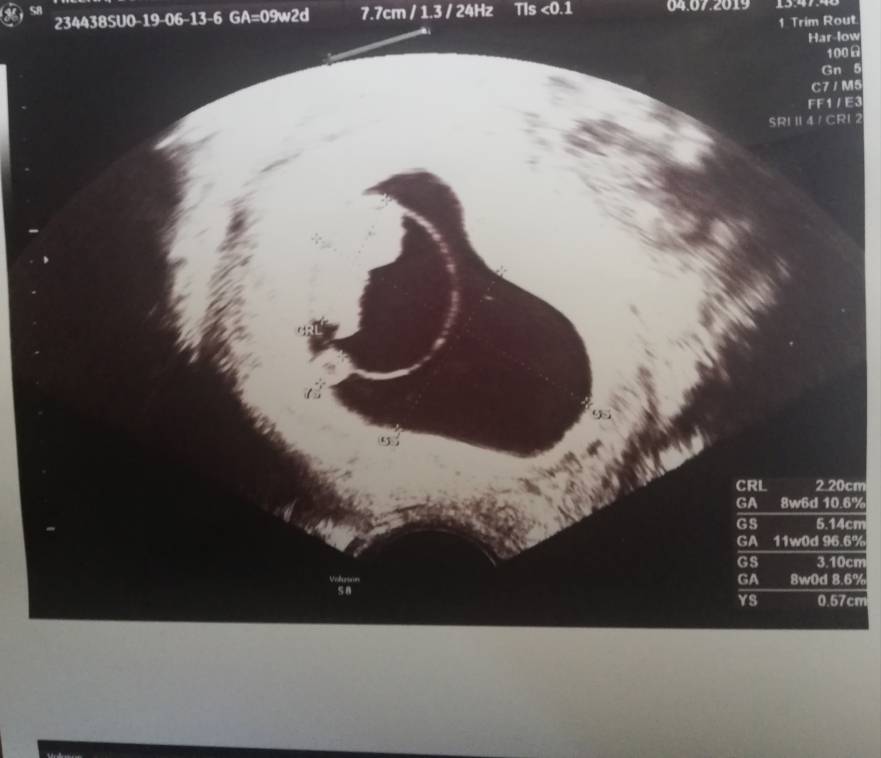

Cześć Dziewczyny przedstawiam Wam mojego maluszka ma 2.20 cm i nawet pomachał nóżkami na USG [emoji6] jak na razie jest wszystko idealnie aczkolwiek dostałam luteine na miesiąc. No i od dzisiaj jestem na L4 [emoji6] trzymam kciuki za resztę [emoji3526]Zobacz załącznik 994175Zobacz załącznik 994176